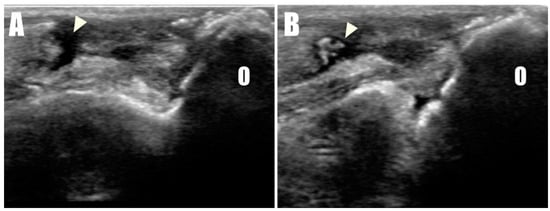

Figure 3. Disruption of the triceps brachii tendon (arrowhead) from the olecranon (O) was confirmed in ultrasonographic images of the (A) right and (B) left sides.

A 2-year-old, 4.5 kg, intact female Pomeranian was referred to a veterinary medicine teaching hospital with bilateral open wounds (Video S1, Figure 1A) at the olecranon region. The dog presented with a history of bilateral forelimb lameness and crouch gait (Figure 1B) as follows: four weeks in the left forelimb and three weeks in the right forelimb, each following a fall from a height. Physical examination revealed a pain response and nodular formation in the proximal region of the olecranon, with no extension response during the triceps brachii squeeze test. Radiographs revealed radiolucent opacities on both sides of the olecranon (Figure 2A,B), and ultrasonography identified defects (Figure 3A,B) at the triceps brachii tendon and olecranon junction, accompanied by inflammation and edema. Notably, the distal end of the proximal tendon appeared hyperechoic compared with the normal tendon. Based on the diagnosis of bilateral triceps brachii tendon disruption, believed to be of traumatic origin, and with the exact cause remaining open to interpretation, surgical repair was indicated. The initial management of the open wounds involved sugar dressing and debridement. Pre-anesthetic evaluation through blood samples, assessing electrolytes, and complete blood count (CBC), revealed all values within normal limits.